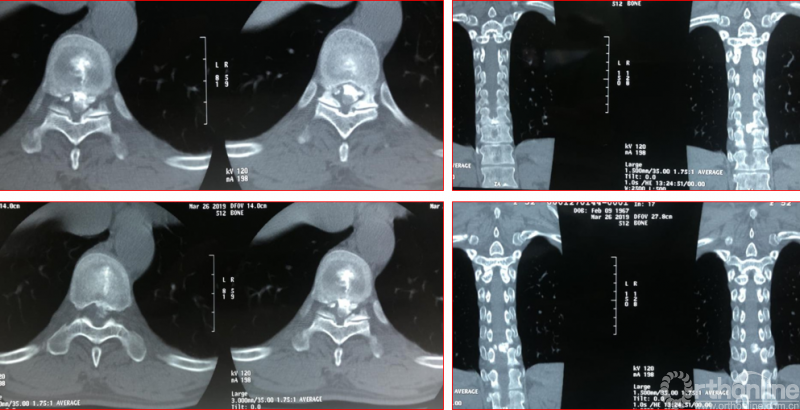

术前资料